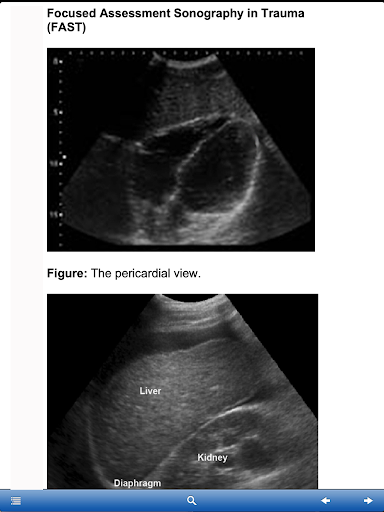

Focused Assessment Sonography Trauma

Please review the screen images before downloading.